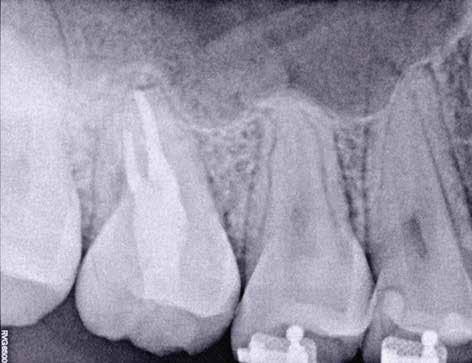

1. a–g. ábrák: A direkt pulpasapkázás lépései. Kiindulási bitewing-felvétel: A meglévő restaurátum közel helyezkedett el a pulpakamrához (a). Kiindulási periapicalis felvétel: Nincs periapicalis elváltozás fennállására utaló jel (b). A pulpaexpozíció (c). A vérzéscsillapítás céljából 20 másodpercen keresztül steril vattagombóccal történő kompressziót követően látható pulpaseb (d). A pulpasapkázás céljából behelyezett anyag, a széli részek tisztázása előtt készült felvétel (e). A röntgenárnyékot nem adó ideiglenes tömés behelyezése után készült felvétel (f). Az első ülés végén a röntgenárnyékot nem adó ideiglenes töméssel ellátott fogról készített röntgenfelvétel (g).

2. ábra: A hat hónapos kontroll alkalmával készített röntgenfelvételen vastag dentinhíd látható a pulpasapkázó anyag alatt.

3. ábra: A hároméves kontroll alkalmával készített röntgenfelvételen megfigyelhető a restaurátum pontos illeszkedése.

A diagnózisunk reverzibilis pulpitis volt. Periapicalis elváltozás jelenlétét nem vélelmeztük. A fogban lévő amalgámtömés eltávolítása során körülbelül egy 3 mm átmérőjű pulpaseb keletkezett a buccalis pulpaszarvnak megfelelően (1. a–g. ábrák) Mivel nem tapasztaltunk jelentős vérzést, és a diagnózisunk reverzibils pulpitis volt, ezért a direkt pulpasapkázás elvégzése mellett döntöttünk.

A kavitást 2,5%-os nátrium-hipoklorit oldattal fertőtlenítettük, majd sűrű konzisztenciájú kalcium-szilikát alapú anyagot (CeraPutty, Meta Biomed) készítettünk elő a direkt pulpasapkázás elvégzéséhez. Az első kezelés végén röntgenárnyékot nem adó ideiglenes töméssel (NexTemp LC, Meta Biomed) zártuk

az üreget annak érdekében, hogy a direkt pulpasapkázásra használt anyag megfelelő pozícióját radiológiailag ellenőrizni tudjuk. A második ülés során kompozit tömőanyagból (Ezfil, Meta Biomed) direkt adhezív restaurátumot készítettünk.

A kezelést követően a beteg tünetmentes volt. A kérdéses fog a kontrollvizsgálatok során végzett szenzibilitástesztekre fiziológiás reakciókat adott. A hat hónapos kontroll alkalmával készített röntgenfelvételen a sérülésnek megfelelően széles dentinhidat észleltünk (2. ábra). A restaurátum a hároméves kontroll során is megfelelőnek bizonyult (3. ábra)